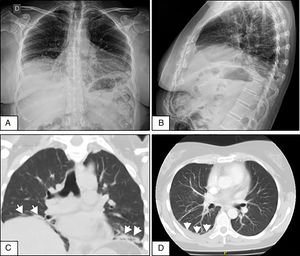

A y B. Radiografías de tórax de frente y perfil que evidencian elevación de ambos hemidiafragmas y atelectasias laminares bibasales. C. Corte coronal de tomografía de tórax sin contraste que demuestra elevación diafragmática y atelectasias subsegmentarias (flechas) en ambas bases pulmonares. D. Tomografía axial computarizada de tórax con contraste que muestra derrame pleural escaso en la base pulmonar derecha (flechas).

Mujer de 50 años que consultó por disnea de medianos esfuerzos de 4 semanas, dolor pleurítico derecho y síntomas constitucionales. Dos semanas previas a la admisión se le realizó radiografía de tórax en la que se evidenció DP leve, sin alteraciones en los volúmenes pulmonares. Se descartó proceso infeccioso y tumoral. Por persistencia de síntomas se repitió radiografía de tórax en la que se evidenció elevación de ambos hemidiafragmas y atelectasias laminares bibasales (figs. 1A y B). Se realizó tomografía y angiotomografía de tórax que confirmaron atelectasias, DP derecho, sin infiltrados ni embolia pulmonar (figs. 1C y D). En radioscopia (sniff test) se observó disminución en la excursión diafragmática bilateral. Se realizó toracocentesis, líquido compatible con exudado. Se objetivó restricción severa y disminución de presiones inspiratoria y espiratoria máximas. La difusión de monóxido de carbono se encontró disminuida. En el test de caminata de 6minutos mostró caída de 5 puntos en la saturación de oxígeno a los 2minutos. Inicialmente negó síntomas sicca. Se evidenció leucocitosis leve, eritrosedimentación elevada, hipergammaglobulinemia policlonal y serologías virales negativas. Se decidió iniciar prednisona 20mg/día hasta disponer de resultados inmunológicos. Los ANA-Hep2, anti-ENA, anti-Ro/SS-A, anti-La/SS-B, anti-ADN y crioglobulinas fueron negativos, complemento normal y factor reumatoide positivo a título bajo. Al mes manifestó xerostomía y xeroftalmia que persistieron por más de 3 meses. Cumplió 4 de 6 criterios clasificatorios americano-europeos 2002 para SSp (síntomas orales y oculares, test de Schirmer menor a 5mm a los 5minutos, puntuación de 6 en la escala de Bijsterveld en tinción con rosa de Bengala y biopsia de glándulas salivales menores con sialoadenitis linfocítica grado 4 de Chisholm y Mason)3. Se diagnosticó SPE en SSp con índice de actividad (ESSDAI)4 de 5. En su evolución presentó vasculitis cutánea linfocítica y polineuropatía sensitivomotora axonal. Cumplió tratamiento con azatioprina 150mg/día y prednisona 40mg/día, con respuesta incompleta y desarrollo de pancitopenia. Se rotó a micofenolato mofetil con respuesta hematológica y cutánea, pero deterioro neurológico y pulmonar (ESSDAI 15). Se administraron 2 dosis de 1g de rituximab cada 15 días y budesonide inhalado. Al mes ESSDAI de 7 y a los 3 meses mejoría de los síntomas respiratorios, normalización de test de caminata, restricción moderada en espirometría, ausencia de derrame pleural, pero persistencia de elevación diafragmática. El índice de daño acumulado de la enfermedad fue de 7 (Sjögren's Syndrome Disease Damage Index)5.